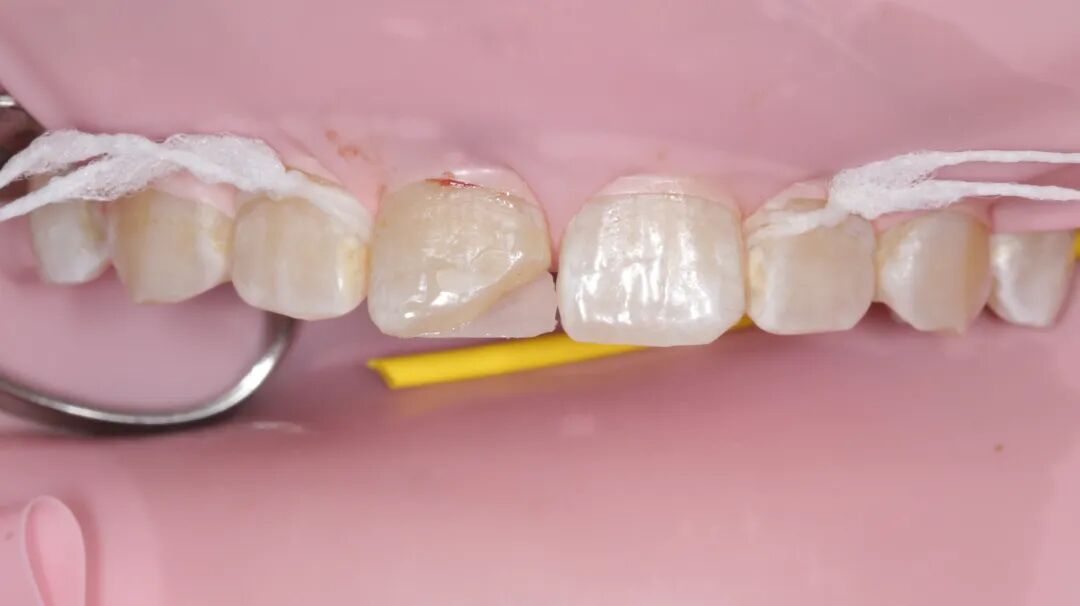

检查:口内右上1近中切角折断,患牙不松动,牙髓活力正常。因患者年龄较小,家长不接受冠修复,沟通后选择树脂修复。取术前观测模型,蜡恢复缺损部位,制作硅橡胶导板。橡皮障夹配合【康田正楔线】障下修整缺损面,【康田正消毒刷】涂布自酸蚀粘接剂,放置导板,流体树脂恢复舌侧基本形态,【康田正豆瓣成形片】恢复邻接形态后唇面常规树脂充填,修型,调合,抛光,康田正邻面抛光条抛光邻面。

◆近中切角折断

◆橡皮障夹配合楔线完成上障,障下对折断面打磨后【康田正消毒刷】涂布粘结剂,放置硅橡胶背板,流动树脂恢复折断部位舌侧面为什么牙医不用开口器特邀牙医【实操病例】集锦{9.22}_https://www.jmylbn.com_新闻资讯_第12张

康田正豆瓣成形片】恢复近中邻接后常规树脂充填,修型